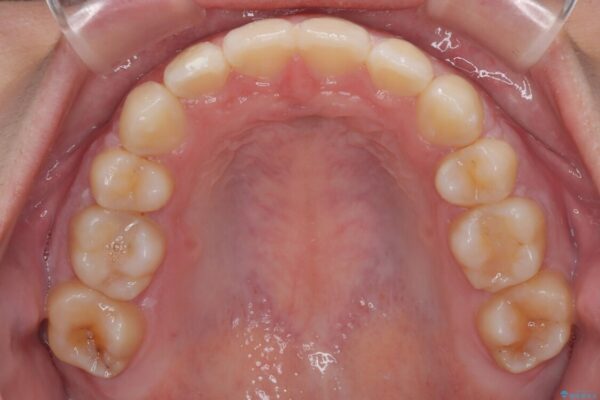

治療後

• 転勤でも安心して治療継続 抜歯スペース閉鎖と深い噛み合わせ改善のワイヤー矯正 治療後画像